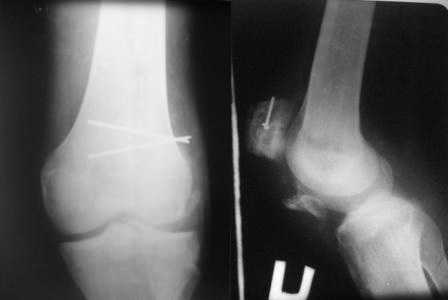

прилагаю  снимки  надколенника.